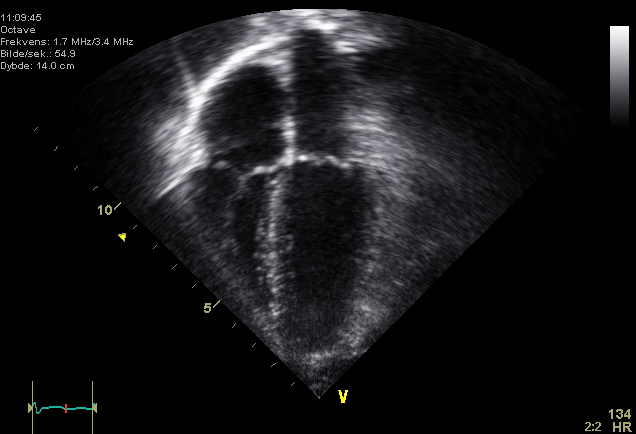

超声心动图四腔心切面:可同时观察左右心房和左右心室的结构与运动